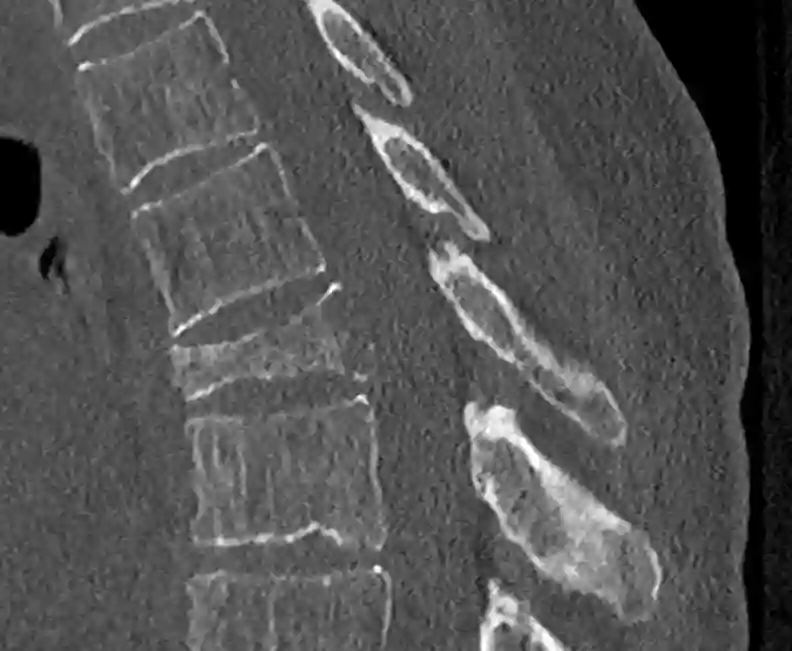

Sinterungsfraktur im CT

Darstellung einer Sinterungsfraktur von BWK6 in einem sagittalen CT Bild der Brustwirbelsäule im Knochenfenster.